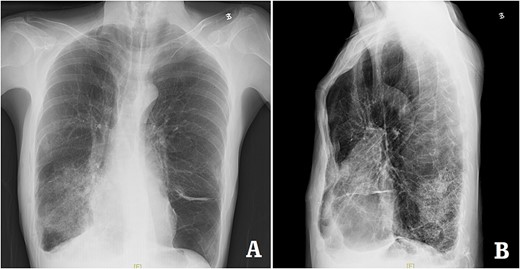

The patient was a 29-year-old male. He was found to have protrusive deformity on the anterior chest wall since childhood. The deformity was not serious in early years, but worsened after adolescence, with the lower part of the sternum protruding at an acute angle. At the age of 25, he developed right spontaneous pneumothorax and received surgical treatment at local hospital, but his thoracic deformity was not treated. As the deformity continued to worsen, which seriously affected the appearance of the chest wall, the patient was admitted to our hospital for surgery. Preoperative physical examination showed that the anterior chest wall was protrusive seriously, with a sharp tip protruding forward. The rib arches on both sides were slightly depressed (Fig. 1). Imaging examination showed that the anterior chest wall was protrusive, and the lower end of the sternum was at the forefront of the protrusion. His heart moved to the right, and the rib arches were slightly depressed (Figs 2–4). The operation was performed under general anesthesia. Two longitudinal incisions were made on both sides of the chest wall respectively. The incisions were located between the front axillary line and the median axillary line, with the length of ~5 cm. The chest wall muscles were dissected to expose the ribs in the incisions. Two tunnels were made on the highest plane of the protrusion, with interval of 3 cm. The tunnels were located in the deep layer of the chest wall muscles and bone structures. Two steel bars were inserted into the tunnels to flatten the front protrusion with their median parts, and then, both ends of the steel bars were fixed on the ribs at the lateral chest wall. The above operation was the main content of Wenlin procedure [1, 2, 5]. After this procedure was completed, the lower part of the chest wall showed obvious depression, especially in the middle of the rib arches. Then, Wung procedure was performed [6]. A third tunnel was made at the plane passing the midpoint of the rib arch, which passes through the bilateral thoracic cavity. The third steel bar was inserted into the tunnel. After the steel bar was rotated and fixed to the ribs, the depression was supported totally. The incisions were closed, and the operation was completed. The deformity of anterior chest wall disappeared completely after the operation (Fig. 5). The operation time was 75 min. The intraoperative bleeding volume was 40 ml. Postoperative X-ray examination showed that the bars position was normal (Fig. 6). He was discharged 7 days after operation. Follow up for 1 year showed satisfactory recovery. The steel bars were taken out 1 year after the operation, and the appearance of the thorax was normal and there was no recurrence (Fig. 7).

X-ray examination after the bars were taken out. (A) Posteroanterior radiograph; and (B) lateral radiograph.